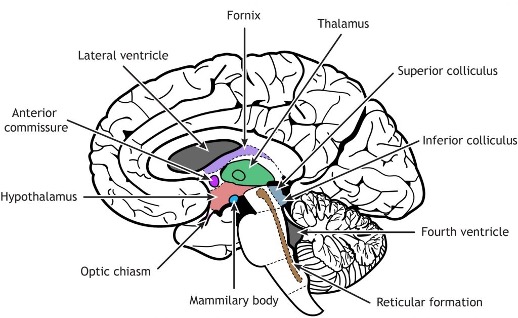

Corpus collosum

Thalamus

Hypothalamus

Brain stem

Mid brain

Pons

Medulla oblongata

Superior (visual) and inferior (auditory) colliculi

What is ‘closed’ vs ‘open’ medulla referring to?

The "open" medulla is where the fourth ventricle opens, forming the dorsal surface, while the "closed" medulla is where the fourth ventricle is surrounded by the medulla, and the central canal is still enclosed.

Thalamus

Hypothalamus

hypothalamic sulcus

separates thalamus from hypothalamus

mammillary body

thalamic adhesion

pineal gland - regulates melatonin

interpeduncular fossa - space between cerebral peduncles.

optic chiasm

fornix- a fiber tract that extends from the hippocampus to the mammillary body